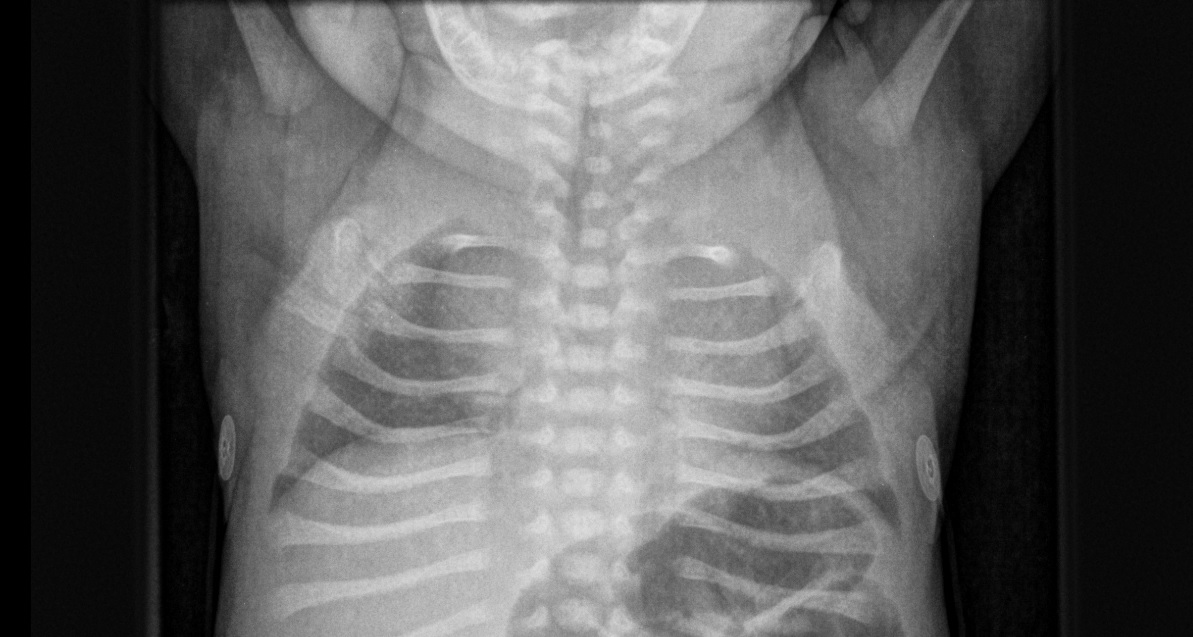

Diagnostic tests. A radiographic skeletal survey demonstrated skeletal dysplasia with absent clavicles (Figure 1), uncalcified skull bones with an absent nasal bone (Figure 2), a bowing deformity of the clivus, sandal gap deformity (Figure 3), and an absent cisterna magna.

Figure 1. Chest radiograph demonstrating absent clavicles.